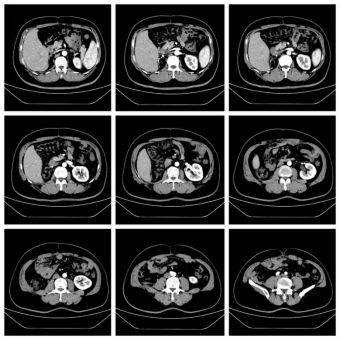

63岁男性,腹膜后脂肪肉瘤术后2年,肿瘤复发3个月。因复发肿瘤导致肠梗阻已无法进食。

我们为患者实施了全麻下开放腹腔肿物切除+回肠部分切除+右侧腹膜后肿物切除+右肾切除+右半结肠切除手术,手术历时2小时,出血200ml以内。术后第1天下地,术后4天排气,术后1周流食,术后10天出院。